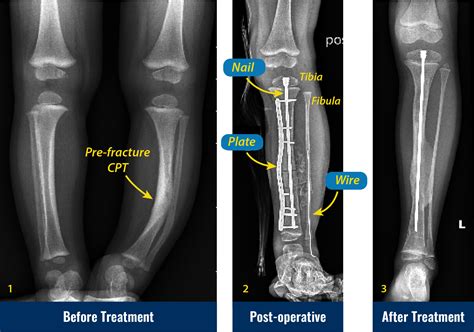

Alright, let’s get to the main event: the pseudoarthrosis tibia X-ray. This is the go-to imaging tool for docs trying to figure out if you’ve got this non-union thing going on. When they suspect pseudoarthrosis, the standard X-ray is usually the first step, and often, it’s enough to give them a pretty good idea. What are they actually looking for on these films, you ask? They’re hunting for signs that the bone hasn’t knitted back together . A healthy fracture healing will show progressive callus formation – that’s new bone trying to bridge the gap. In pseudoarthrosis, you’ll often see a clear gap between the broken bone ends, and instead of solid bone bridging it, there might be fibrous tissue or even cystic changes in the bone ends. Sometimes, the bone ends can become rounded off and sclerotic (that means hardened and denser) because they’re not being used properly, and the body’s trying to adapt to the instability. Another key indicator is motion at the fracture site . While you can’t directly see motion on a static X-ray, the consequences of that motion are visible. You might see widening of the fracture line over time, or displacement of the bone fragments that wouldn’t happen if the bone were solidly healed. They’ll also look at any hardware – like screws, plates, or rods – that might have been put in during initial surgery. Is the hardware intact? Is it loose? Is there any sign of infection around it (like bone resorption or bone spurs)? The X-ray is basically a detective’s magnifying glass, revealing clues about the past injury and the body’s current, failed attempt at repair. It’s essential to compare current X-rays with previous ones if available, as this allows the radiologist and orthopedic surgeon to track the progression (or lack thereof) of healing over time. This comparison is vital in confirming a diagnosis of pseudoarthrosis, as a single X-ray might not always be definitive, especially in the early stages of non-union.

What Radiologists Look For on a Pseudoarthrosis Tibia X-Ray

Radiologists are like the skilled detectives of the medical world when it comes to interpreting X-rays. For a pseudoarthrosis tibia X-ray , they’re scrutinizing the image with a fine-tooth comb. The primary goal is to identify lack of bony union . This means they’re looking for a distinct gap between the fractured bone ends. In a successfully healing fracture, this gap would be filled with callus, a new bone formation that gradually ossifies. In pseudoarthrosis, this callus is either absent, inadequate, or has failed to mature into solid bone. They will specifically look for atrophic changes , which means the bone ends are thin, pointed, or have lost their normal shape due to disuse and lack of stability. Conversely, they might see hypertrophic changes , where the bone attempts to heal by forming excessive, often disorganized, bone spurs (callus) around the ends, but these spurs don’t actually bridge the gap. This is often called